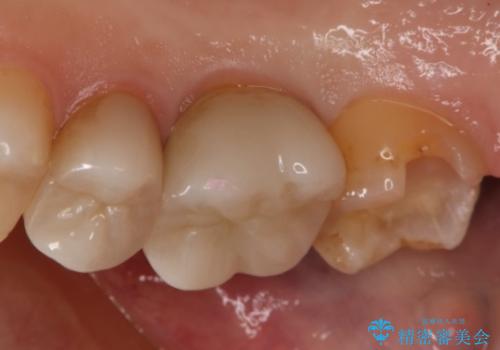

- 右上7番の銀歯のやりかえを主訴に来院された患者様です。

切削量・形態を考慮し、セラミックインレーでの治療を計画しました。